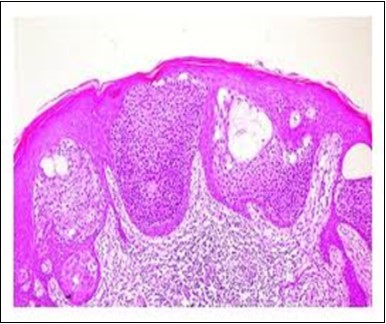

Granular arrangement of malignant cells and intercellular bridges are conspicuous with the demonstration of nuclear atypia, pleomorphism, prominent mitosis and tumour necrosis. A peripheral palisade is discernible within the cellular aggregates. Mitotic figures are common and can be quantified as up to 12 mitosis/ high power field. Tumour differentiation can prominently be of the ductal category with the demonstration of intra-cytoplasmic lumina. Comedo type tumour necrosis is evident along with foci of squamous differentiation The neoplasm is reactive to periodic acid Schiff ‘s (PAS) stain. (Figure 1, Figure 2, Figure 3, Figure 4, Figure 5, Figure 6, Figure 7, Figure 8, Figure 9, Figure 10, Figure 11, Figure 12, Figure 13.

Figure 3.Cohesive accumulations with numerous ductular articulations of carcinoma cells in eccrine porocarcinoma (15).

The neoplasm is composed of lobules of aberrant epithelial cells configured in cords with incrimination of the dermis and epidermis.. Malignant cells congregate within the epidermis or infiltrate the dermis, especially in the primary tumour. Tumour cells within tumour aggregates display a well demarcated cellular outline and appear distinct from encompassing squamous cells. Numerous tumour cell clusters demonstrate a cystic lumen. Prominent epidermal acanthosis is discerned on account of tumour cell proliferation 6, 7.

Eccrine porocarcinoma is an infiltrative, high grade tumour which is contiguous with superimposed epidermis, depicts a partially lobular architecture and a diameter usually exceeding > 90 millimetres. An endophytic pattern of tumour evolution is elucidated with invasion of deep reticular dermis and subcutaneous tissue 5, 6.

Eccrine porocarcinoma on morphological elucidation depicts the incrimination of cutaneous structures, foci of ulceration along with multiple areas of cellular infiltration. Tumefaction arises from basal layer of skin.